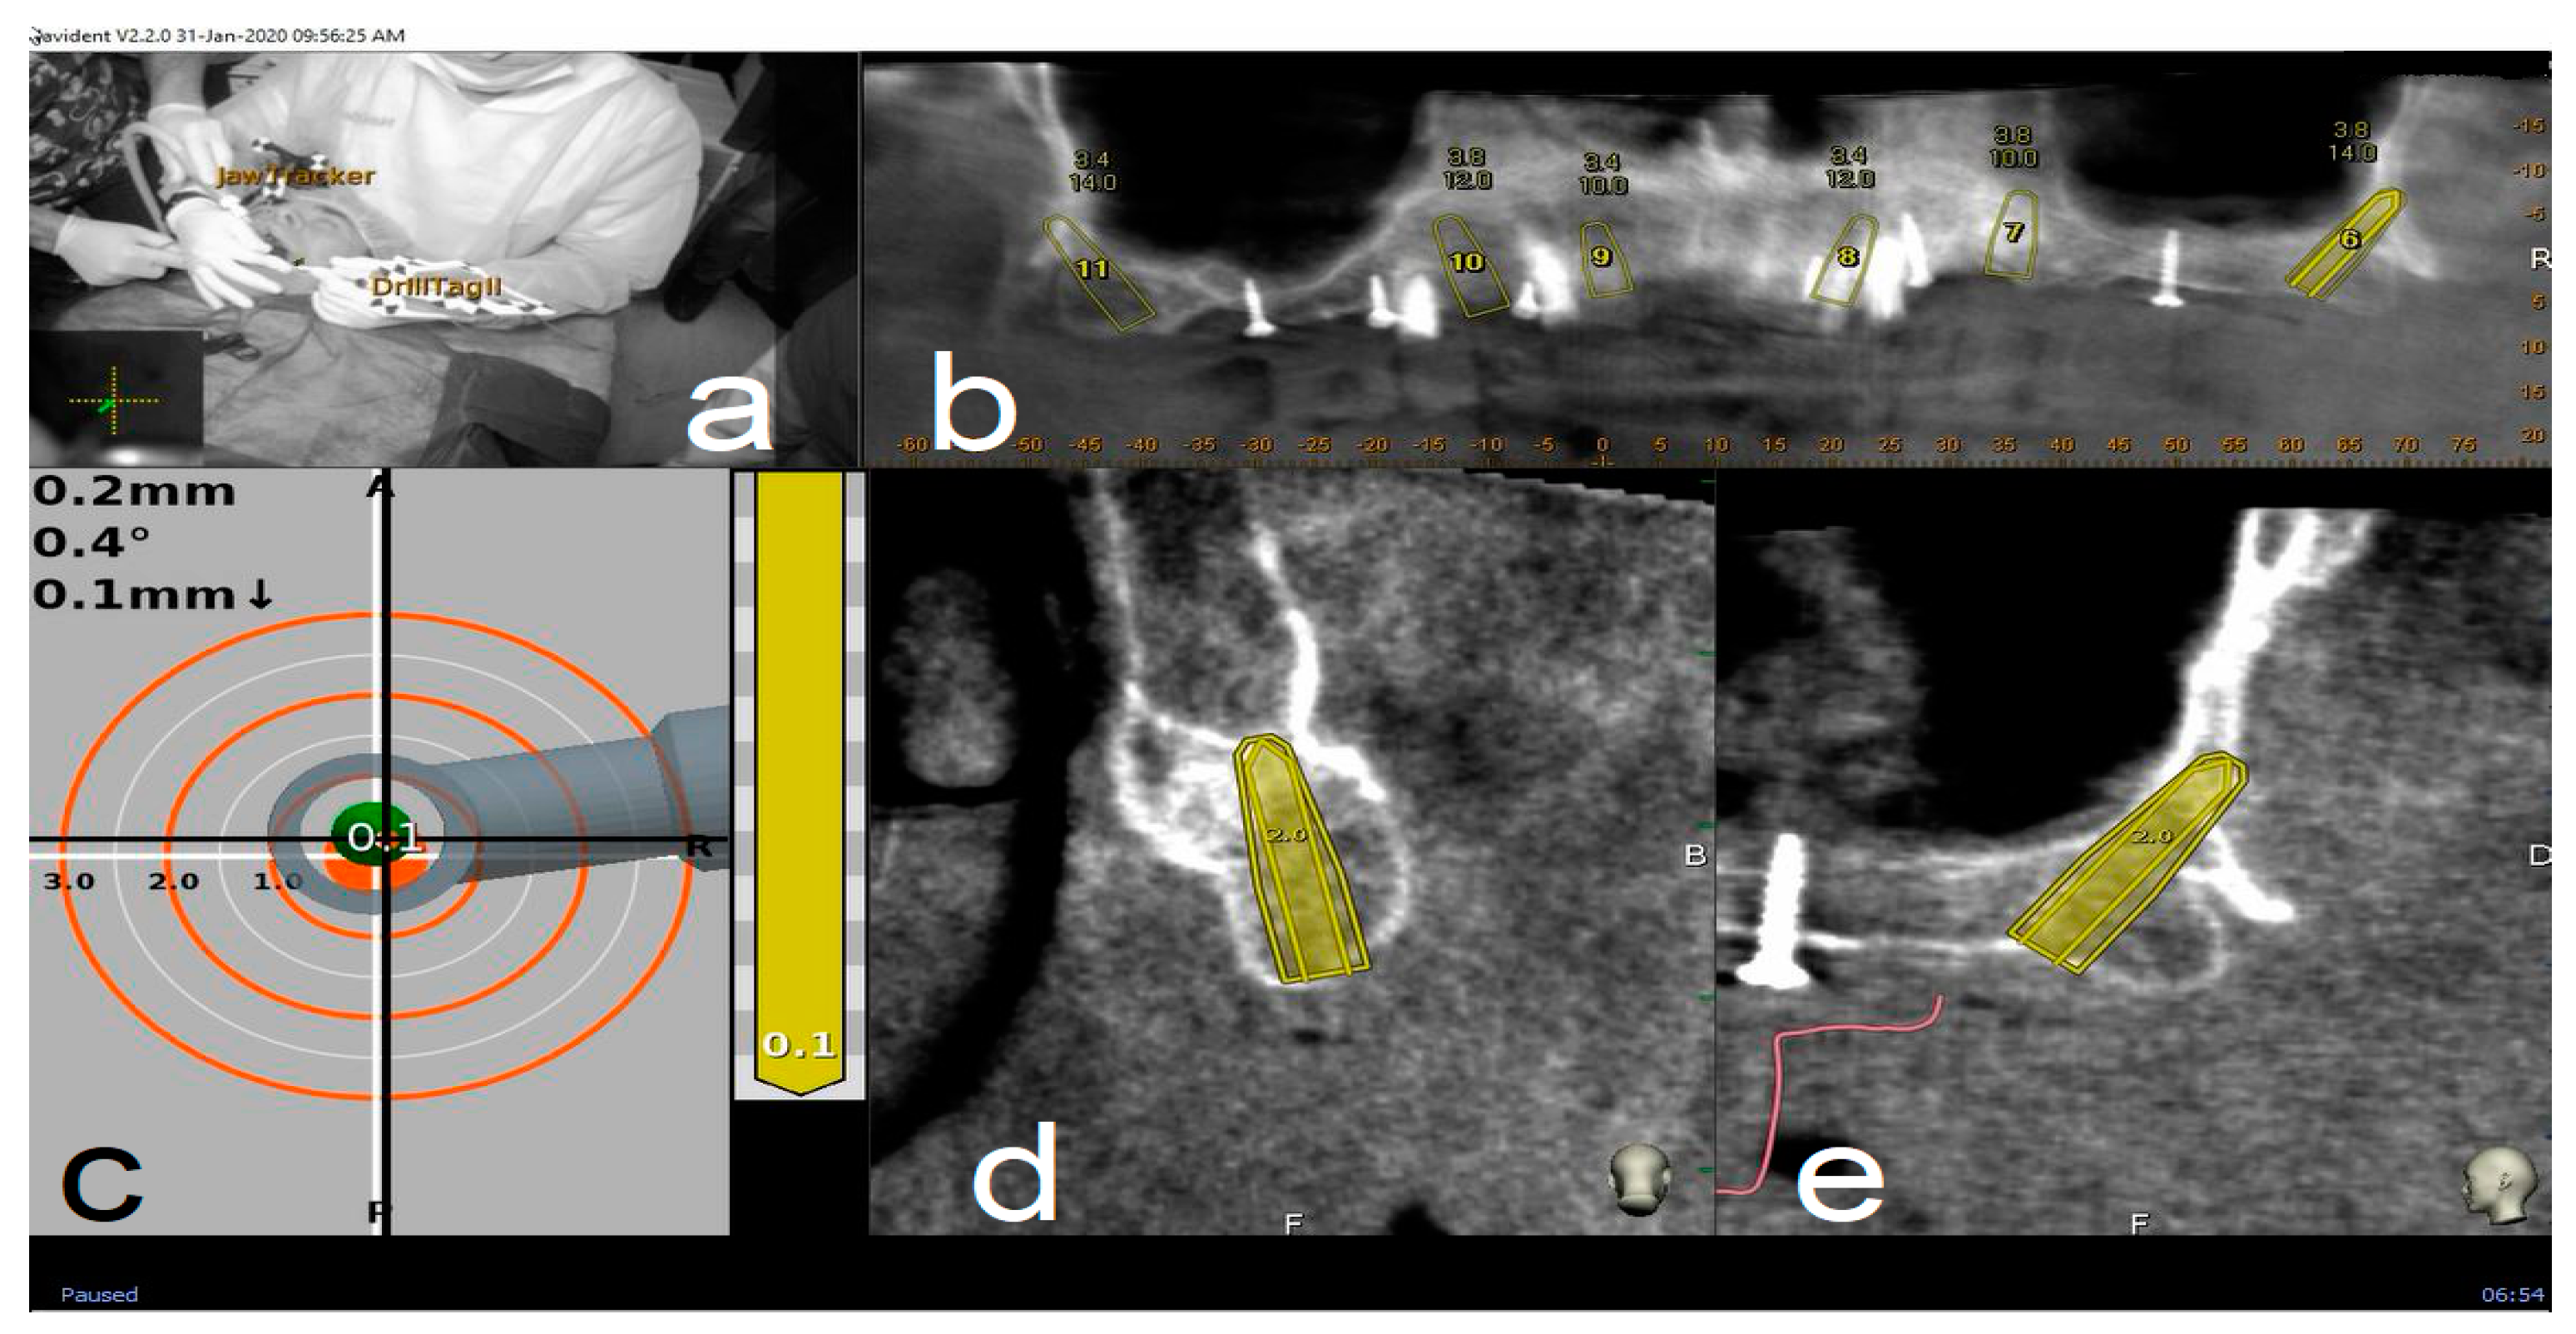

2.4.3. Place

Handpiece drill axis and drill tip length are then calibrated using a metallic caliber; a second accuracy check is carried out in the same manner as for tracing. Once accuracy is confirmed, navigated implant placement can be carried out following target view. This allows clinician to verify, in real time, entry point, depth, and angulation of planned osteotomy as related to the plan. Other views that the clinician can see on the screen enable her/him to follow the position of the handpiece drill during osteotomy in coronal and sagittal views (Figure 5).

Figure 5.

Clockwise from up left. The figure indicates the several views on the screen during surgery: tracker video stream (a), panoramic view (b), target view and depth indicator (c), bucco-lingual section view (d), and mesio-distal section view (e).